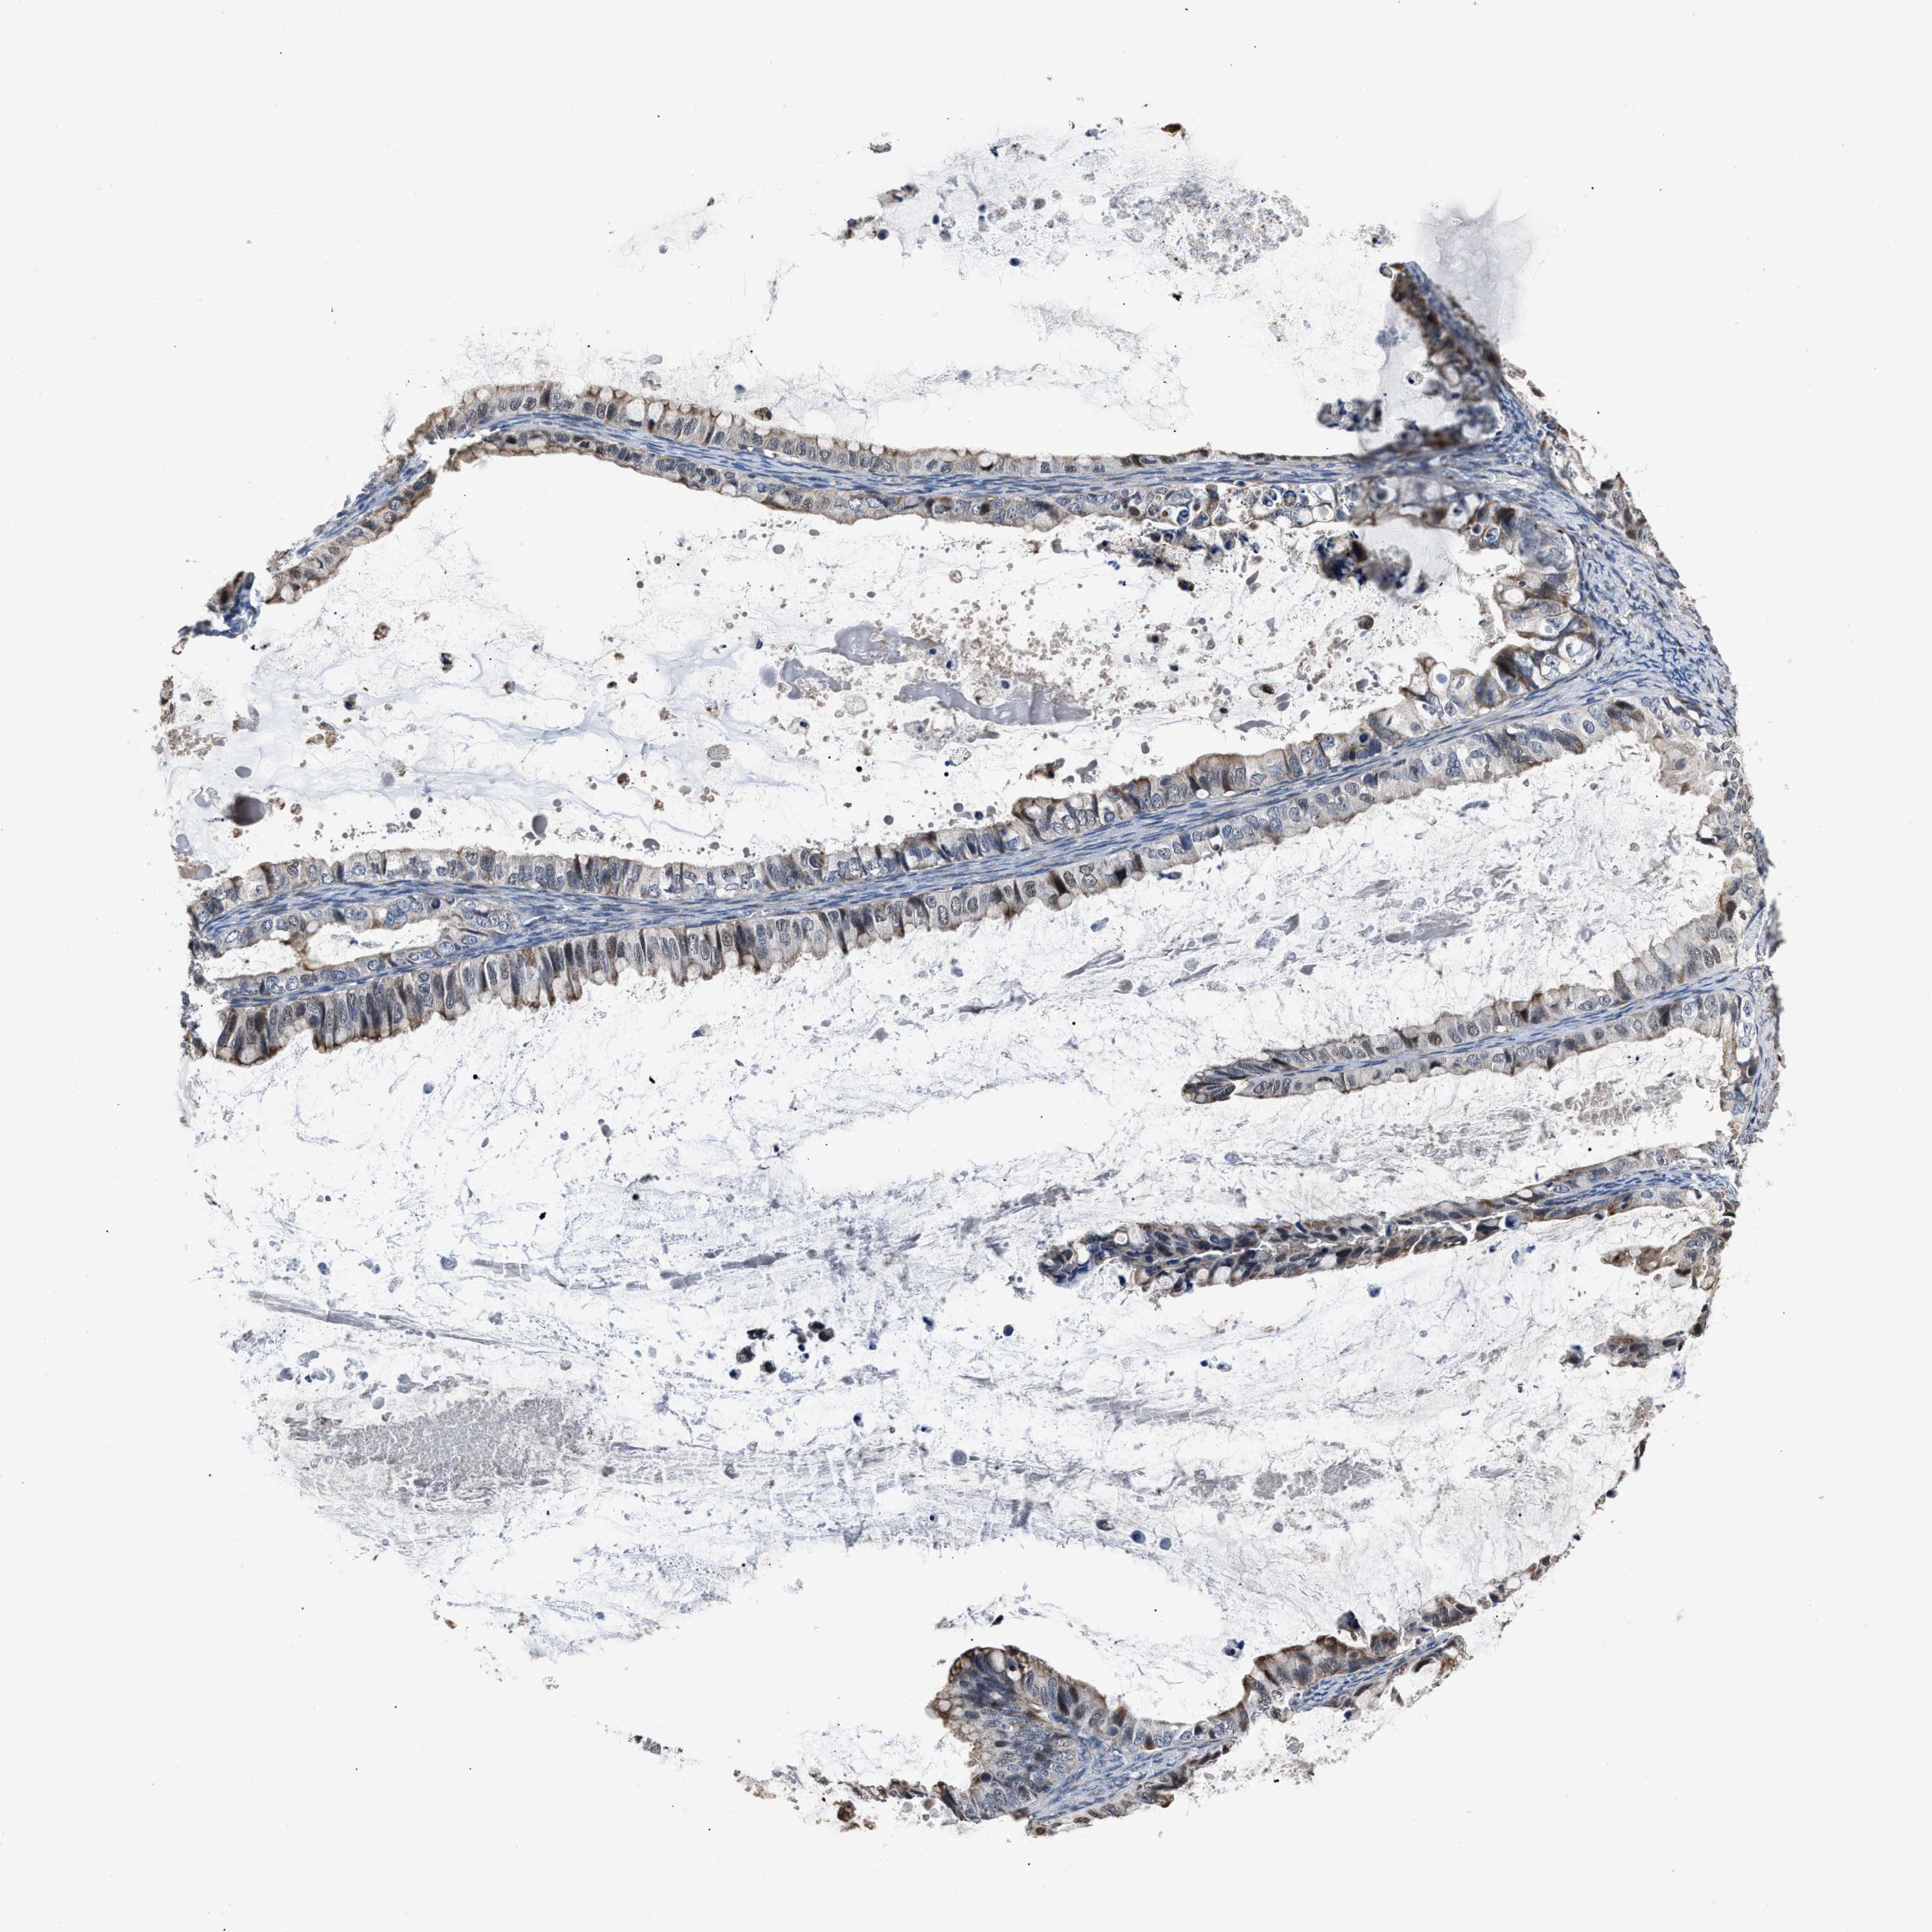

OVARIAN CANCER - Protein expressioni

A mouse-over function shows sample information and annotation data. Click on an image to view it in a full screen mode. Samples can be filtered based on level of antibody staining by selecting one or several of the following categories: high, medium, low and not detected. The assay and annotation is described here.

Note that samples used for immunohistochemistry by the Human Protein Atlas do not correspond to samples in the TCGA dataset.

Antibody stainingi

Antibody staining in the annotated cell types in the current human tissue is reported as not detected, low, medium, or high, based on conventional immunohistochemistry profiling in selected tissues. This score is based on the combination of the staining intensity and fraction of stained cells.

Each image is clickable and will lead to virtual microscopy that enables deeper exploration of all samples and also displays staining intensity scores, fraction scores and subcellular localization as well as patient and tissue information for each sample.

Antibody HPA020536

Staining

High

Medium

Low

Not detected

Intensity

Strong

Moderate

Weak

Negative

Quantity

>75%

75%-25%

<25%

None

Location

Nuclear

Cytoplasmic/membranous

Cytoplasmic/membranous,nuclear

Cystadenocarcinoma, serous, NOS

Carcinoma, endometroid

Cystadenocarcinoma, mucinous, NOS

Carcinoma, NOS